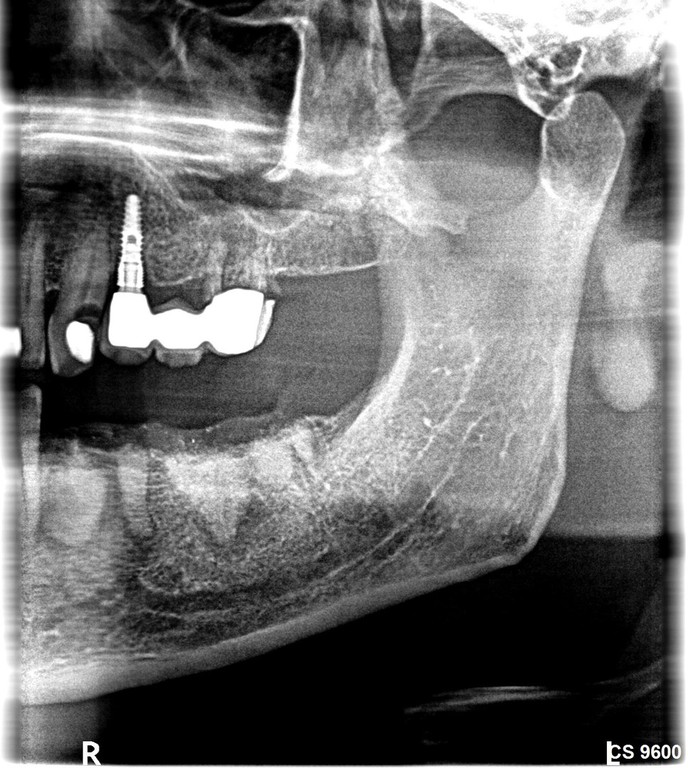

Ridge + Implantation 4 Jahre Follow up

Extraktion 34, 35, 36, 37, Ridge ohne Membran, Adaptionsnähte, Rö Kontrolle, Wundheilung 1, 4, 12 und 23 Tage nach OP. Knochensituation bei Reentry nach 4 Monaten.  Implantation Regio 34 und 36  ( 2 x  5,5 x 13mm). Freilegung nach 2 Monaten und ZE Eingliederung  2 Wochen später. Klinisch und radiologisch 4 Jahre nach Ridge.